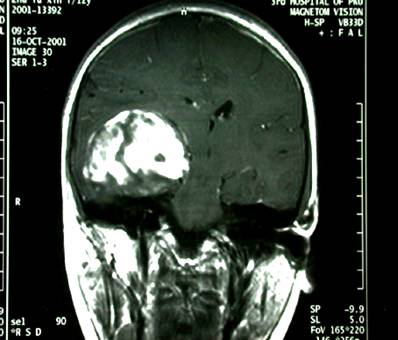

右颞深部胶质瘤

男性,40岁,主因,癫痫发作入院,查MRI示:右颞胶质瘤。

术前影像